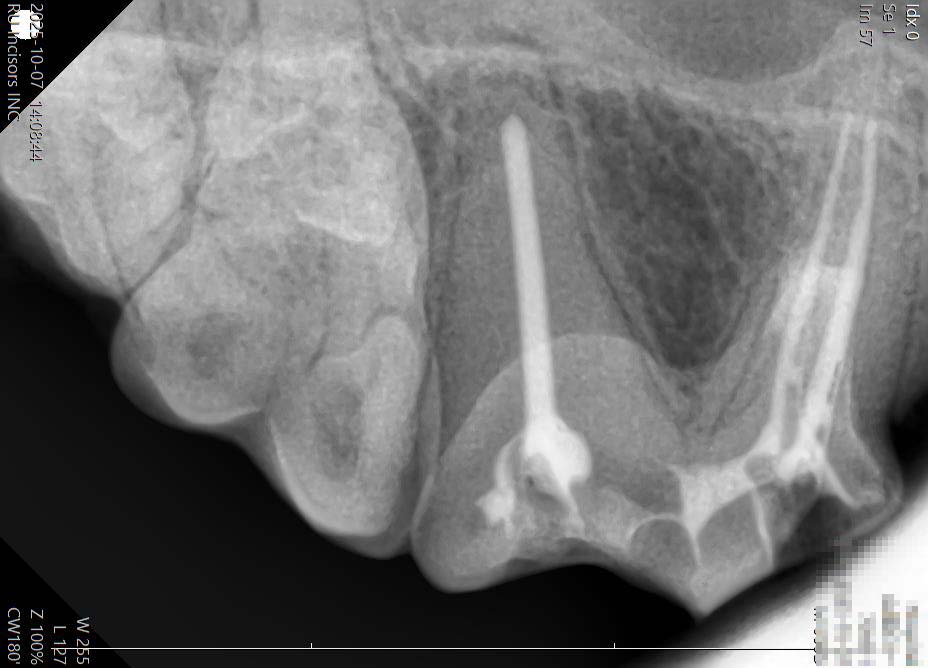

歯科レントゲンの活用

当院では歯科治療の際に歯科レントゲンを活用し、目に見えない部分まで正確に把握しています。これにより、安全で確実な手術や治療を行うことができ、飼い主様にも安心して頂けます。

口腔内の視診や触診を行い、歯石の付着具合や歯肉の炎症、口臭の有無などを確認します。必要に応じてレントゲンや血液検査なども行い、治療方針を検討します。

スケーリングによる歯石除去や、必要に応じた抜歯を行います。全身麻酔下では歯科レントゲンを活用し、見えない部分まで確認しながら安全かつ確実な治療を実施します。